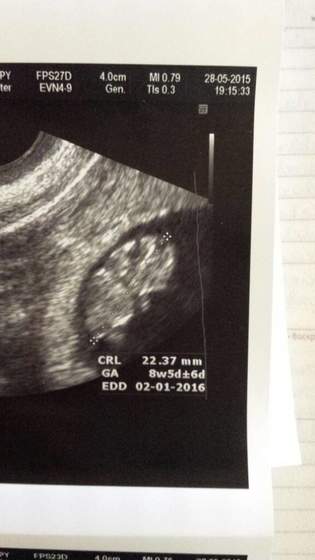

u nas wg usg 8t4d :) Żuczek misiaczek ma 22mm, serducho bije jak oszalałe, nawet juz sie rusza :):)

Zaraz zrobie zdjecie fotki :) dostałąm tez te z poprzedniej wizyty, której jak się okazało ginka zapomniała mi dac :)

• 1432837543140.jpg

1432837543140.jpg

17,3 KB · Wyświetleń: 63